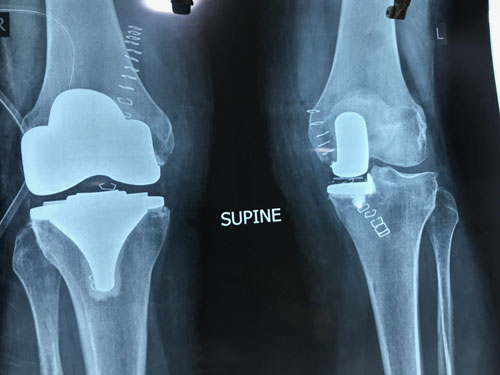

55-year-old lady had a windswept deformity; she was bow-legged on one side and had a knocked-knee on the other. A rare deformity and extremely difficult to match the alignment.

We performed a PCL retaining Total Knee Replacement on the knocked-knee and Partial Knee Replacement on the bow leg to achieve accurate alignment.